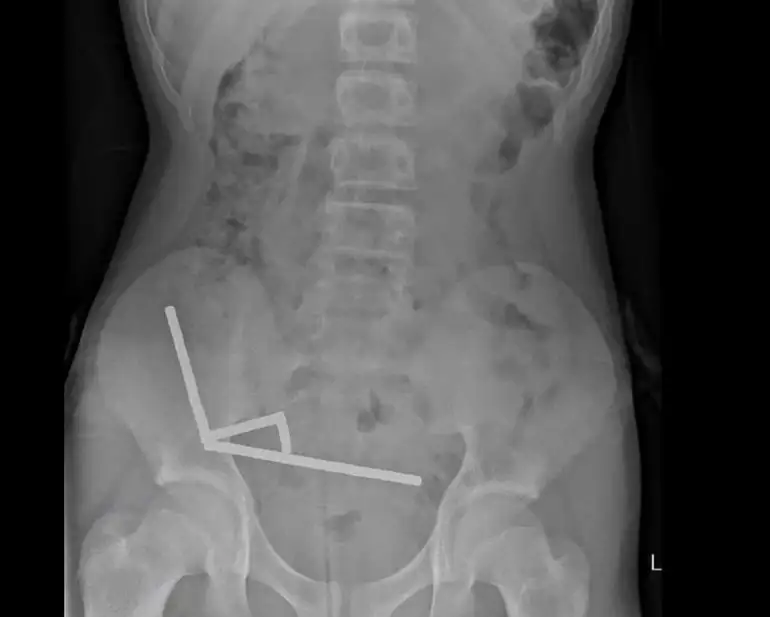

Μια ακτινογραφία έδειξε ότι οι μαγνήτες είχαν σχηματίσει σε τέσσερις ευθείες γραμμές μέσα στα έντερα του παιδιού.

«Φαινόταν να βρίσκονται σε ξεχωριστά μέρη του εντέρου και να έχουν κολλήσει μεταξύ τους λόγω μαγνητικών δυνάμεων», ανέφεραν.